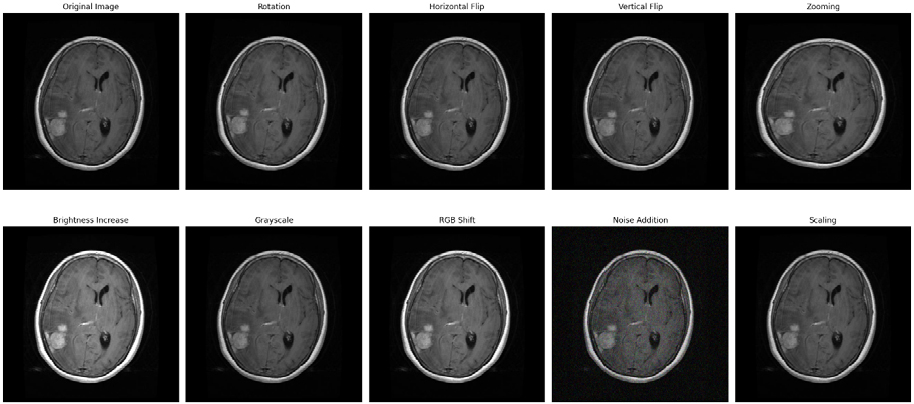

Each original images has undergone to preprocessing steps consists of applying 9 different augmenting techniques on each image [43]. Image augmentation techniques includes Horizontal flip, Vertical flip, rotation, Adjustment on Brightness, resizing & zooming, Filtering like mode & sobel filter, grayscale conversion, unsharp masking, and & noise addition are added to make 9 times of original dataset.

MRI scan augmentation involves modifying images by adjusting orientation, size, appearance, and adding variations to enhance model robustness and generalization as shown in Figure 7. Nine augmentations techniques were applied on merged dataset of 20,690 original MRI images to create the 185,580 improvised images.